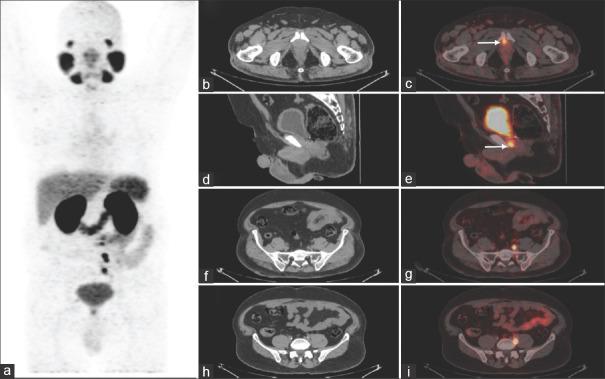

The study included 170 men, all had adenocarcinoma of the prostate, 124/170 had previous RP and 46/170 had prior RT. The median serum PSA in the RP group was 1.8 ng/ml and 5.2 ng/ml in the RT group. In the post-RP cohort, the detection rate of Ga PSMA PET/CT was 39.3% for PSA 0.2 to <0.5 ng/ml, 47.3% for PSA 0.5 to <1 ng/ml, 68.4% for PSA 1 to <2 ng/ml and 93.1% for PSA ≥2 ng/ml. In the post-RT group, the detection rate was 88.8% for PSA 2 to <4 ng/ml and 100% for PSA ≥4 ng/ml.

该研究纳入了170名男性,均为前列腺腺癌,其中124/170曾接受过RP,46/170曾接受过RT。RP组血清PSA中位数为1.8 ng/ml,RT组为5.2 ng/ml。在RP后队列中,PSA 0.2至<0.5 ng/ml时Ga PSMA PET/CT的检出率为39.3%,PSA 0.5至<1 ng/ml时为47.3%,PSA 1至<2 ng/ml时为68.4%,PSA≥2 ng/ml时为93.1%。在RT后组中,PSA 2至<4 ng/ml时检出率为88.8%,PSA≥4 ng/ml时为100%。